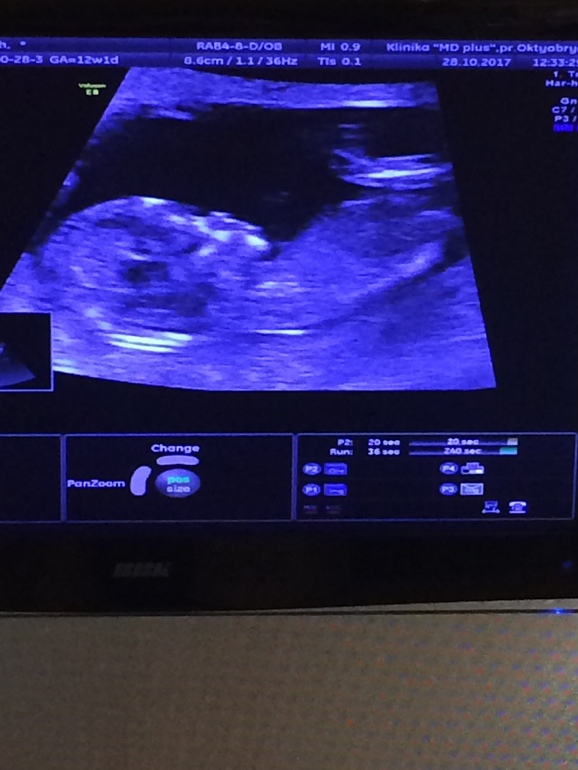

Как думаете кто по Узи?😊💖😊

Вопросы про УЗИ, обследования и анализы: что, где, как, когда?Срок по Узи 12,6 недель чсс 171/уж.мин

На таком сроке в таком ракурсе не понять. Половые бугорки нужно сравнивать в профиль, у девочек и мальчиков на таком сроке одинаково, только углом наклона согласно позвоночника отличается. Можешь посмотреть, в меня в дневнике статья есть по этому поводу. Может, ты на УЗИ и видела малыша в таком ракурсе? Если видела в профиль-можно догадаться кто в домике живёт)))) я нашла эту статью, а на УЗИ уже сама догадалась кто, ещё до того, как врач сказала)

Ага,читала)но лялька вертелась,трудно было уловить,вот и думаю может опытные мамочки подскажут)